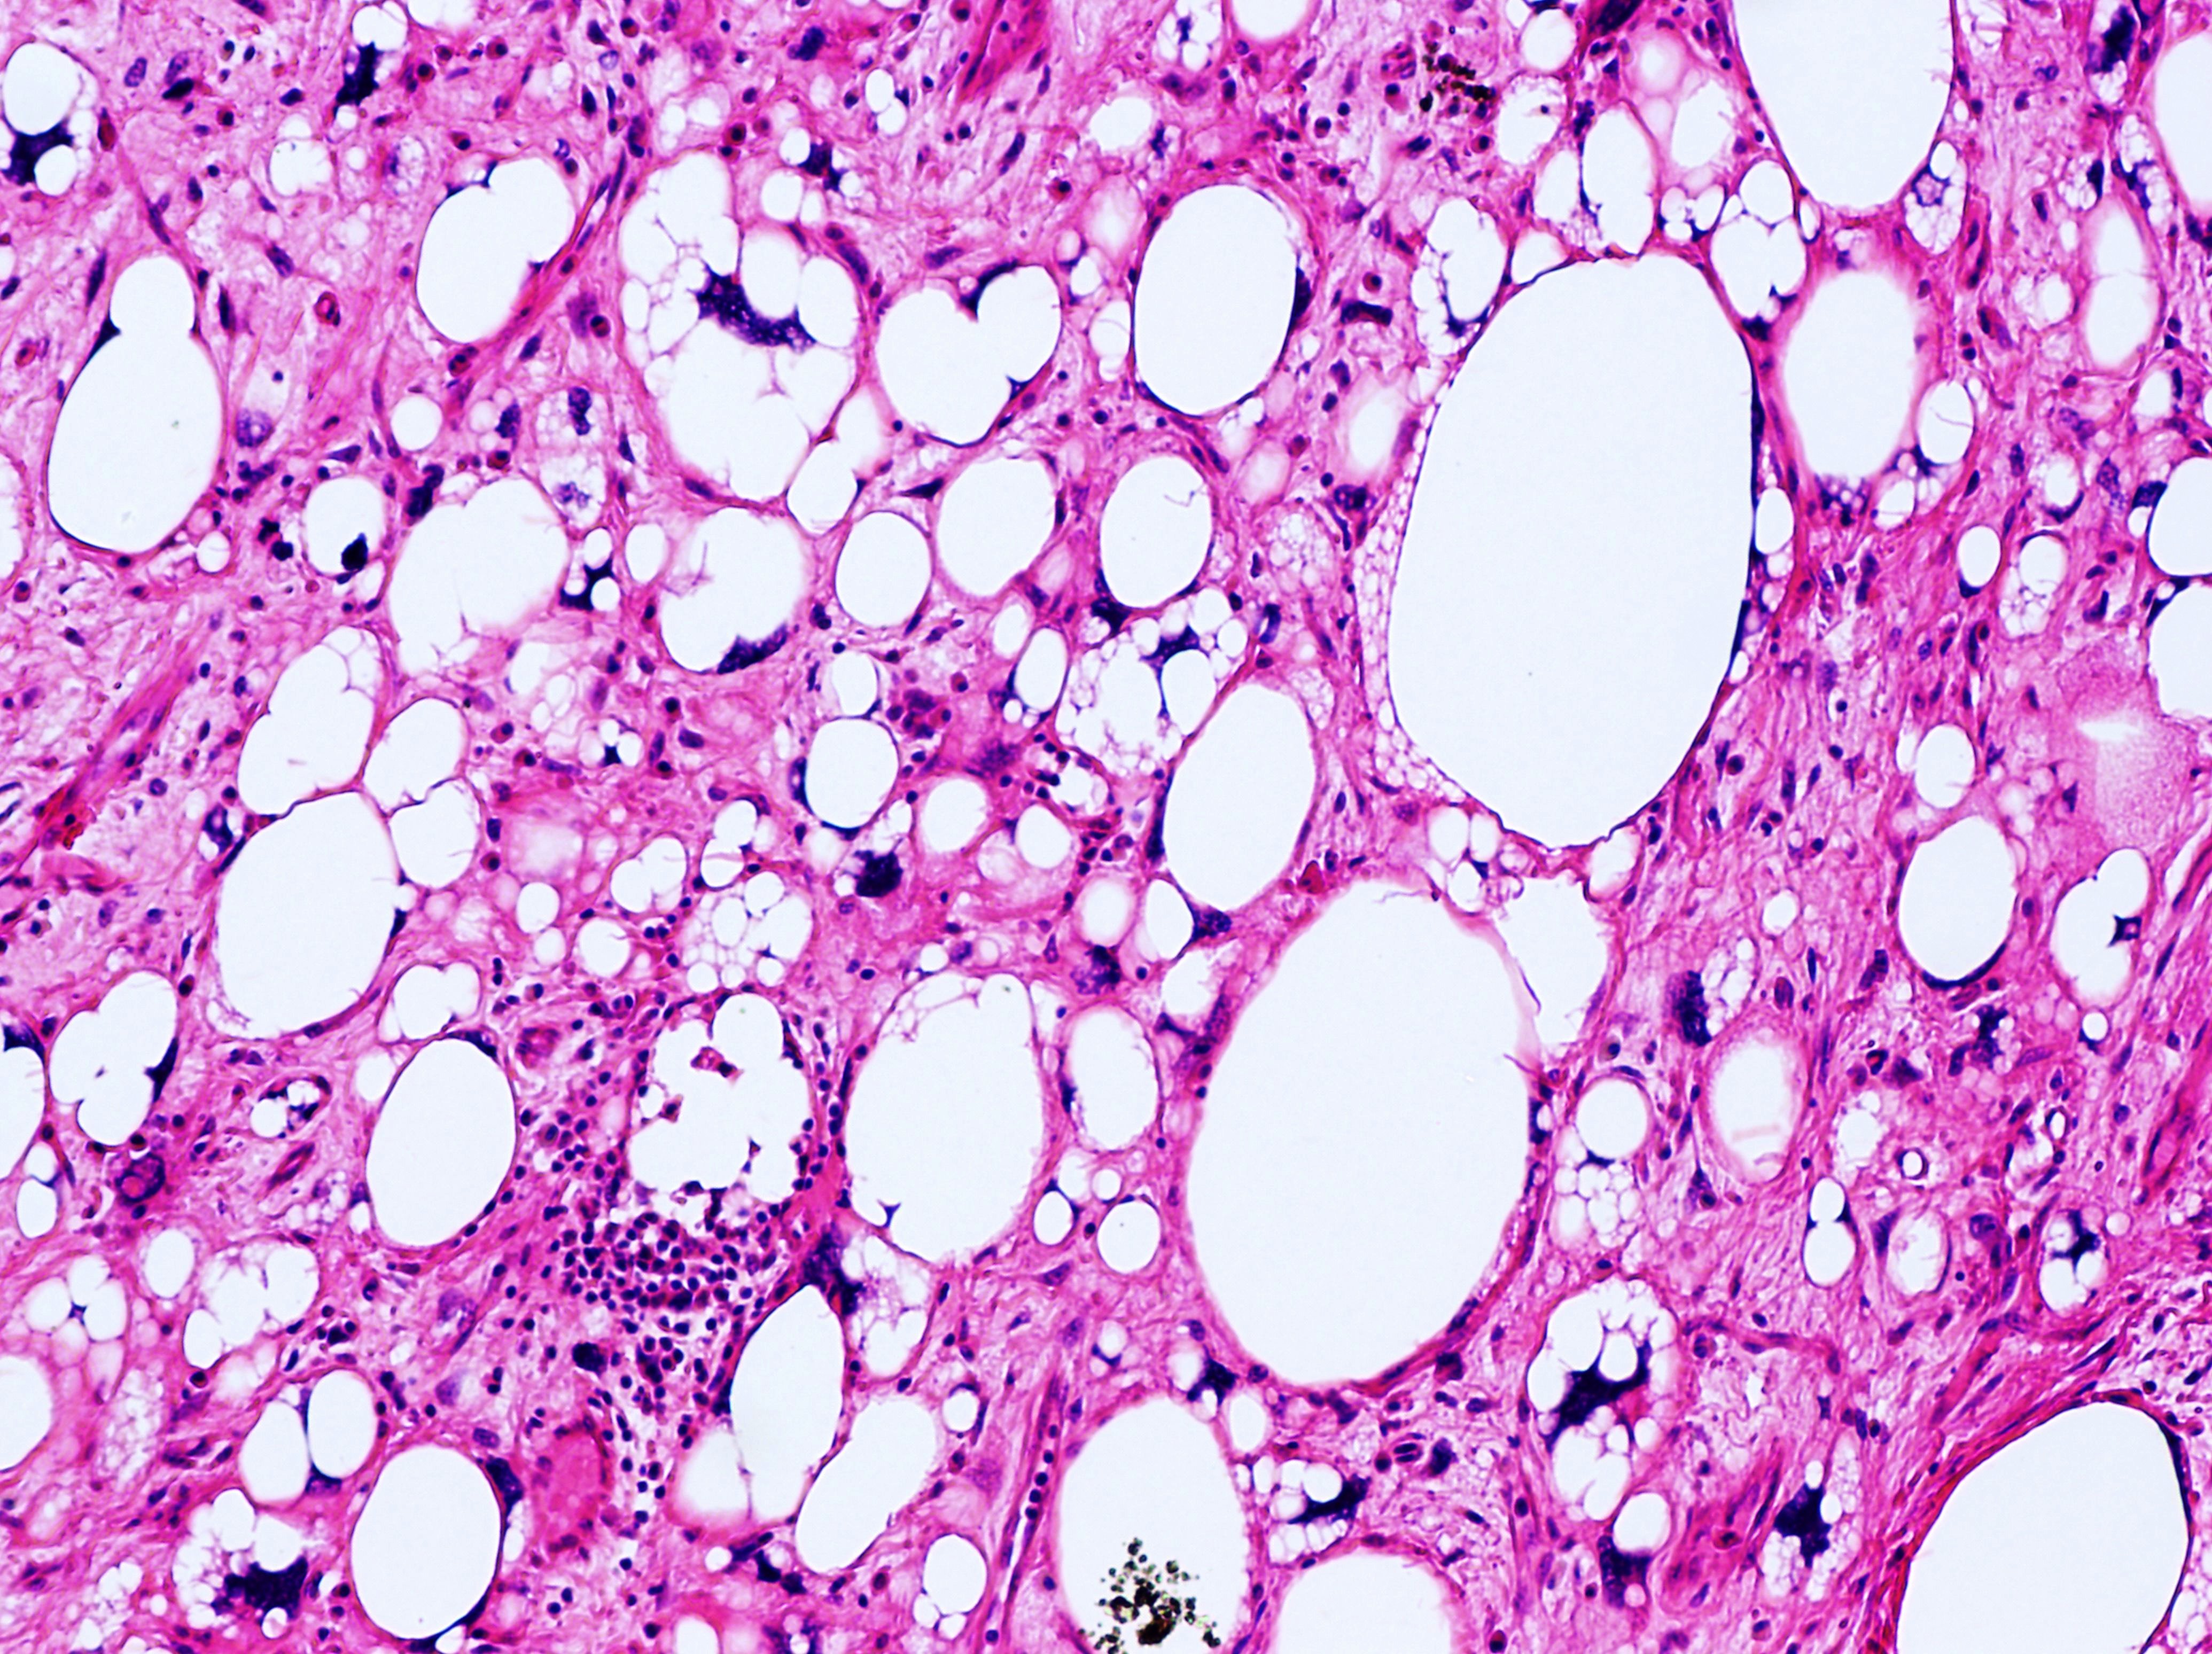

• Anatomical Pathology: This branch of pathology involves the examination of tissues removed from the body during surgery or biopsy to diagnose diseases such as cancer, infections, and inflammatory conditions. Anatomical pathologists analyze tissue samples under a microscope and may use various staining techniques to identify abnormalities.